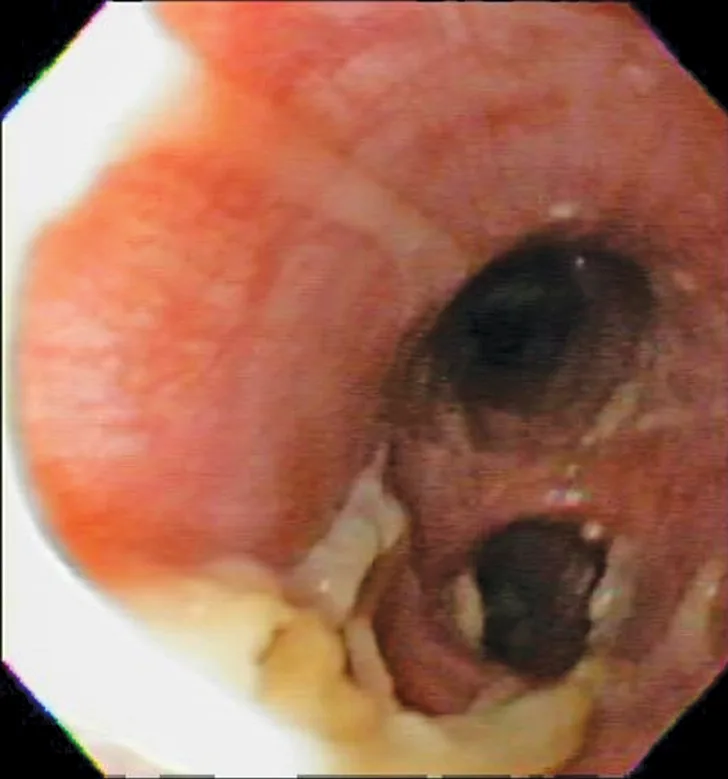

Bronchoscopy results demonstrating mucosal irregularity, hyperemia, and characteristic greenish-yellow airway exudate

Bronchoscopic visualization revealed a moderate amount of thick, adherent, greenish-yellow mucus in the trachea and secondary and tertiary bronchi; mucosa was moderately irregular and erythematous (Figure 2). There was no evidence of airway collapse. Samples were collected via bronchoalveolar lavage for cytology, aerobic culture, and Mycoplasma spp culture.

Cytologic evaluation of the airways confirms eosinophilic inflammation, which is the hallmark of diagnosis. The percentage of eosinophils (mean, 61% of the total nucleated cell population4) exceeds that of healthy dogs (5%-24%).2,5,10 Samples can be obtained via tracheal wash or bronchoscopy. Bronchoscopy allows for visualization of more characteristic airway associated changes (eg, greenish-yellow secretions, irregular mucosa, hyperemia).2,5,11 Occasionally, intraluminal granulomas may be present,4 allowing for mucosal brush samples or biopsies that can further support a diagnosis. Tracheal washes provide appropriate cytologic samples in most cases. Bronchoscopy is generally reserved for patients with more focal radiographic disease, concerns for neoplasia, or suspicion for concurrent structural disorders (eg, bronchial collapse, tracheal collapse).